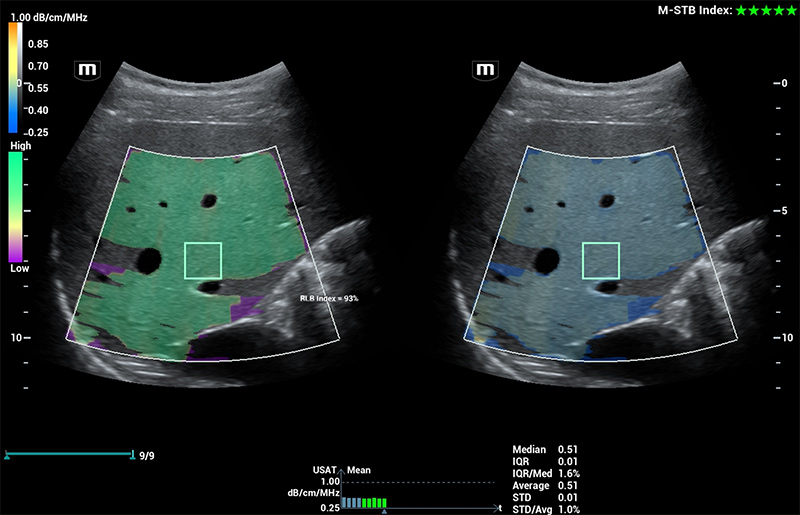

Für die Ultraschalltechnologie stellt die ZST+-Plattform einen bedeutenden Fortschritt dar, da sie statt der herkömmlichen Strahlformung die Kanaldatenverarbeitung verwendet. Diese bahnbrechende Innovation löst übliche Zielkonflikte zwischen räumlicher Auflösung, zeitlicher Auflösung und Homogenität des Gewebes auf, woraus sich eine beispiellose Bildqualität ergibt, die den Weg frei macht für unendlich viele Bildgebungslösungen.

Das Resona I9 weist umfassende klinische Lösungen für spezielle Anwendungen auf. Auf der Grundlage gründlicher Analysen verschiedener klinischer Szenarien liefert es Innovationen, die den Benutzenden herausragende Klarheit, außergewöhnliche Intelligenz und eine erhöhte Diagnosesicherheit bieten.